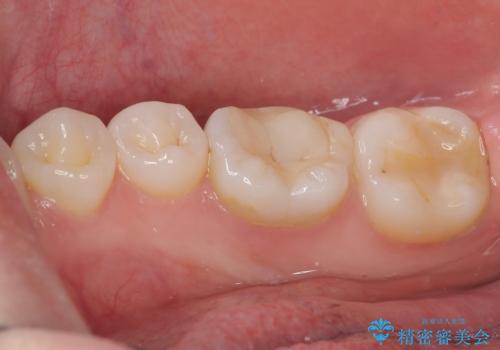

その後、ファイバーコア(グラスファイバー製の支台)を築造し、最終的には精密な適合性と審美性に優れたオールセラミッククラウンによる補綴をしました。

このセラミッククラウンは、歯科技工士と連携し、1本1本の形・色・噛み合わせまで細部にこだわって製作しており、見た目の自然さだけでなく、長期的に安心して噛める機能性も重視しています。